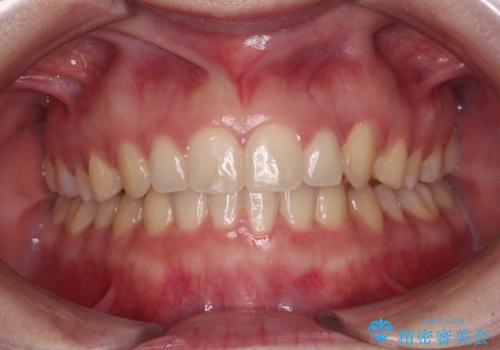

- 前歯のデコボコを気にして来院された患者様です。

叢生と捻転が随所に認められるものの、マウスピースで十分対応可能であったため、インビザラインにて矯正治療を行うこととしました。

マウスピース矯正は毎日しっかりと装着することがとても大切です。

こちらの方はしっかりと指示を守って装着してくださったため、予定通り治療を終えることができました。